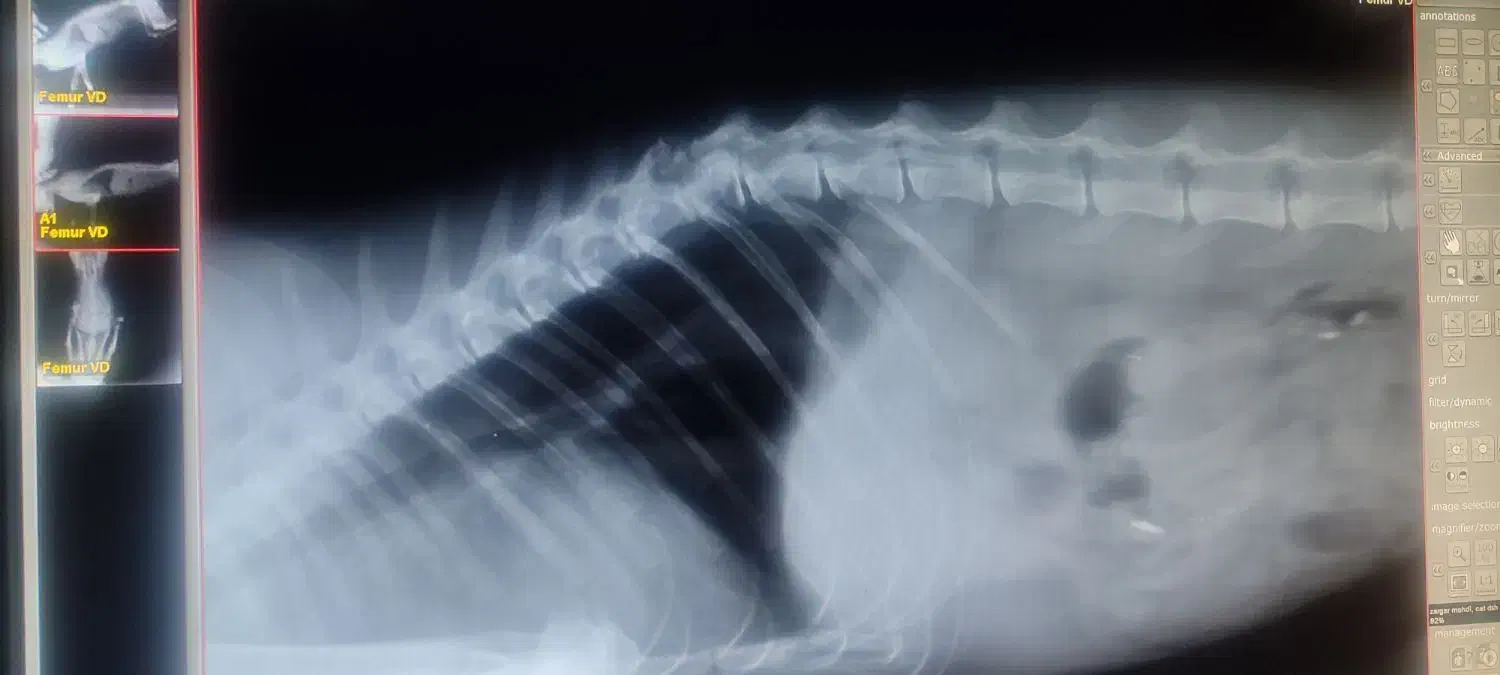

سلام من یه گربه تصادفی پیدا کردم ۱ هفته هم نگهداریش میکنم دکتر هم بردم عکس هم گرفتن جزعی کمرش زربه خورده دکتر گفته خوب میشه از کسی که شرایط نگهاریشو داره خواهشن تماس بگیره ممنون چون من صبح میرم سر کار شب میام نمیتونم کامل بهش برسم